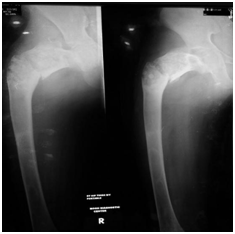

A 16 year-old boy presented to us with right hip pain in 2016. Clinical examination demonstrated shortening of the right lower limb with painful hip movements and inability to weight bear. There was also a well-healed surgical scar over the right hip. Plain radiograph of the hip revealed a subthrocanteric fracture on a background of fibrous dysplasia with a shepherd's crook deformity (Figure 1).

Figure 1 Plain radiograph of the hip revealed a subthrocanteric fracture on a background of fibrous dysplasia with a shepherd's crook deformity.

The patient was allowed partial weight bearing for the first 1 month and gradually progress to full weight bearing. At 3 months the patient was pain free on the Ilizarov frame, he demonstrated almost full range of movement of the hip and walk with less shortening. Radiograph at 6 months showed union at the fracture. At 10 months follow up, radiograph showed thickening of the cortex around the fibrous dysplasia lesion and increased bone density which replaced the cystic lesions (Figure 3). The frame was removed at 10 months post surgery.

Figure 3 Radiograph showed thickening of the cortex around the fibrous dysplasia lesion and increased bone density. a. At 10 months on Ilizarov apparatus. b. After removal of Ilizarov apparatus.